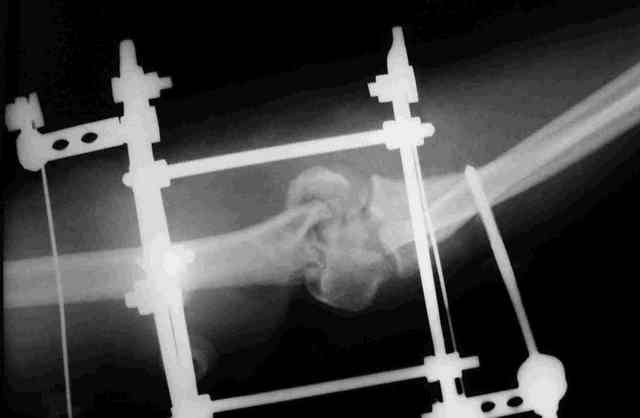

Прошу оказать помощь в определении дальнейшей тактики лечения открытого оскольчатого

перелома дистального отдела плеча, осложненного гнойной инфекцией у пациентки с

сочетанной травмой.

Пациентка получила сочетанную травму в результате падения с высоты. В числе прочих

повреждений открытый оскольчатый перелом дистального отдела плечевой кости. Выполнено

ПХО, гипсовая иммобилизация. На следующие сутки клиника гнойной инфекции. Произведена

вторичная гнойная хирургическая обработка раны, стабилизация перелома аппаратом,

вакуумное дренирование. В настоящий момент гнойного отделяемого нет. (отделяется

синовиальная жидкость. Наложены вторичные швы. Вопрос - какова дальнейшая тактика в случае

заживления раны ( открытый остеосинтез или функциональное лечение). Что делать в случает

возобновления гнойного процесса.